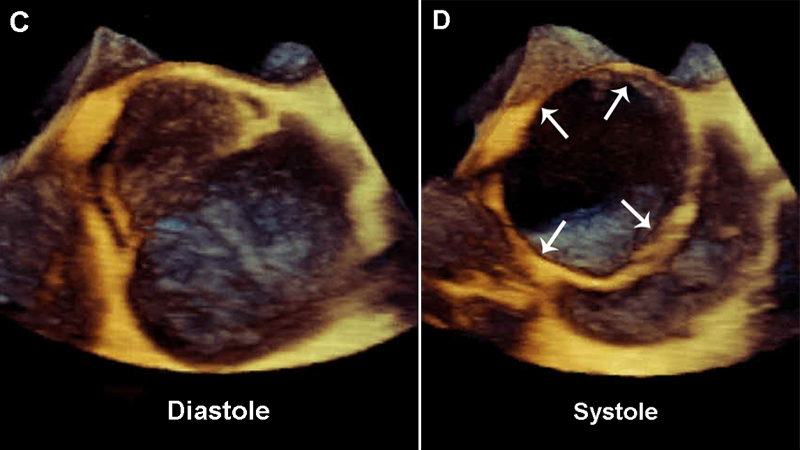

فحوصات تشخيصية لبعض امراض القلب والشرايين التاجية